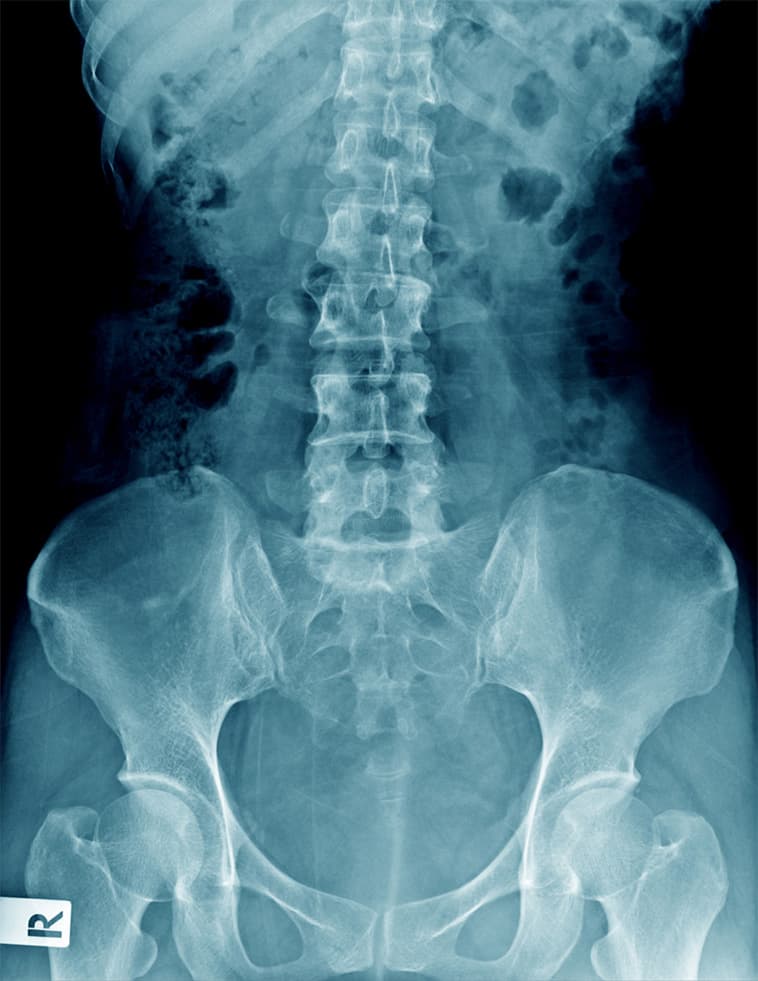

Specialista in patologie del ginocchio, come la gonartrosi e le lesioni meniscali, e dell'anca, con particolare attenzione alle tecniche di chirurgia protesica, inclusa l'innovativa via anteriore mininvasiva.